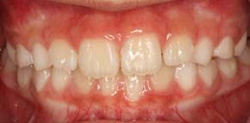

6、過蓋咬合(噛み合わせが深い)

・混合歯列期からからの治療を推奨します。

成長期のお子さんで、骨の大きさに問題があるために噛み合わせが深くなってしまっている場合、成長期の初期段階で治療を始め、上下の顎の成長を適切に管理していくことが好ましいとされています。

骨格的な問題の場合は、治療が遅れてしまうと後で大きな手術が必要になってしまうというリスクがありますので、まずはお子さまの不正咬合がどのような問題から引き起こされているのか、正しい診断を受けることが大切です。

また過蓋咬合の場合は、噛み合わせが深いために前方や側方への顎機能運動にも障害が生じてしまいます。

将来の顎関節や筋機能への影響などという面から見ても、まずは早めに相談されることをおススメします。